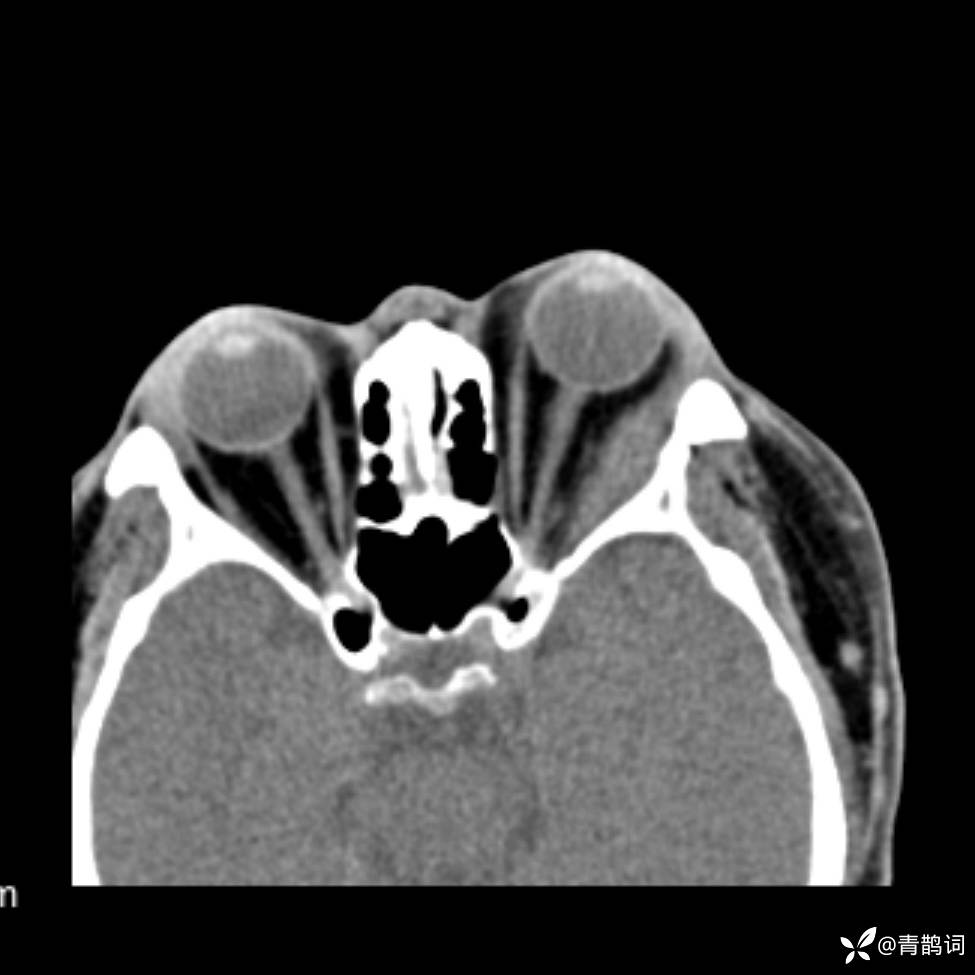

患者年龄:30岁。

患者性别:男。

简要病史:左颜面部肿胀2年,反复咳嗽咳痰,逐渐加重。

结合病史及影像学表现,期待评论区各位老师各抒己见~

木村病 (14)